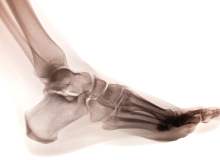

Charcotmarietooth Hastalığı

Charcotmarietooth hastalığı, diğer adıyla kalıtsal motor ve duyusal nöropati, kollarınızdaki ve bacaklarınızdaki sinirleri etkileyen bir grup kalıtsal bozukluktur.